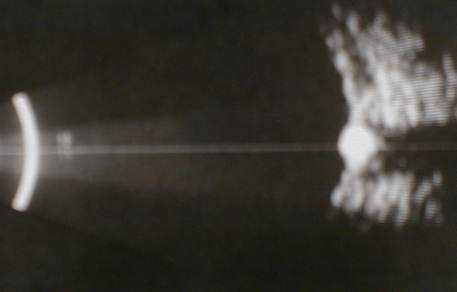

Of the three B scans above can

you differentiate asteroid hyalosis from vitreous haemorrhage?

The scans usually show white opacities

within the vitreous cavity. The main differential

diagnosis being : vitreous haemorrhage,

asteroid hyalosis and synchysis scintillans.

-

The three may look similar on the ultrasound

but in the case of vitreous haemorrhage they

may be associated posterior vitreous

detachment or retinal tear.